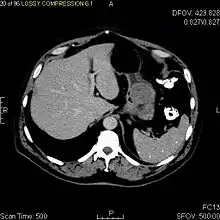

The purpose of radiologic imaging is to locate the lesion, evaluate for signs of invasion and detect metastasis. Features of GIST vary depending on tumor size and organ of origin. The diameter can range from a few millimeters to more than 30 cm. Larger tumors usually cause symptoms in contrast to those found incidentally which tend to be smaller and have better prognosis.[4][13] Large tumors tend to exhibit malignant behavior but small GISTs may also demonstrate clinically aggressive behavior.[14]

Large GISTs

As the tumor grows it may project outside the bowel (exophytic growth) and/or inside the bowel (intraluminal growth), but they most commonly grow exophytically such that the bulk of the tumor projects into the abdominal cavity. If the tumor outstrips its blood supply, it can necrose internally, creating a central fluid-filled cavity with bleeding and cavitations that can eventually ulcerate and communicate into the lumen of the bowel. In that case, barium swallow may show an air, air-fluid levels or oral contrast media accumulation within these areas.[14][17] Mucosal ulcerations may also be present. In contrast-enhanced CT images, large GISTs appear as heterogeneous masses due to areas of living tumor cells surrounding bleeding, necrosis or cysts, which is radiographically seen as a peripheral enhancement pattern with a low attenuation center.[13] In MRI studies, the degree of necrosis and bleeding affects the signal intensity pattern. Areas of bleeding within the tumor will vary its signal intensity depending on how long ago the bleeding occurred. The solid portions of the tumor are typically low signal intensity on T1-weighted images, are high signal intensity on T2-weighted images and enhanced after administration of gadolinium. Signal-intensity voids are present if there is gas within areas of necrotic tumor.[15][18][19]

Features of malignancy

Malignancy is characterized by local invasion and metastases, usually to the liver, omentum and peritoneum. However, cases of metastases to bone, pleura, lungs and retroperitoneum have been seen. In distinction to gastric adenocarcinoma or gastric/small bowel lymphoma, malignant lymphadenopathy (swollen lymph nodes) is uncommon (<10%) and thus imaging usually shows absence of lymph node enlargement.[13] If metastases are not present, other radiologic features suggesting malignancy include: size (>5 cm), heterogeneous enhancement after contrast administration, and ulcerations.[4][13][20] Also, overtly malignant behavior (in distinction to malignant potential of lesser degree) is less commonly seen in gastric tumors, with a ratio of behaviorally benign to overtly malignant of 3-5:1.[4] Even if radiographic malignant features are present, these findings may also represent other tumors and definitive diagnosis must be made immunochemically.